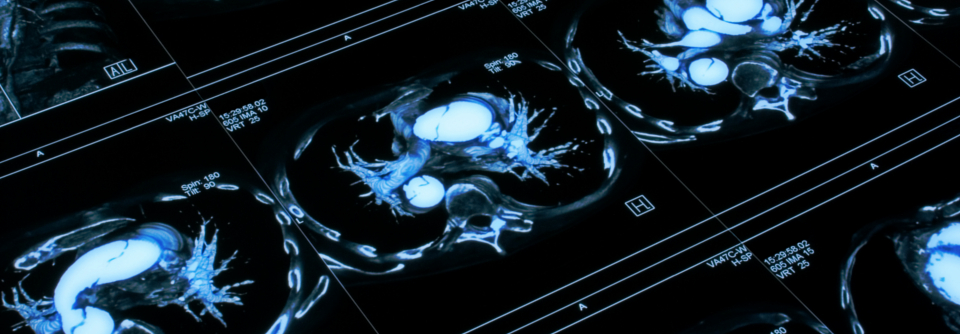

Eine offene Operation ist bei Frauen häufiger der Fall. Eine offene Operation ist bei Frauen häufiger der Fall. © chanawit – stock.adobe.com